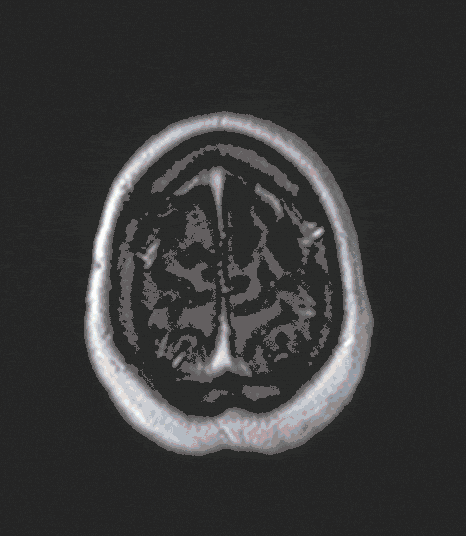

Metastases

In the context of cancer (lung cancer, breast cancer, malignant melanoma, etc.), unfortunately, metastases can also spread to the brain and lead to neurological deficits or seizures.